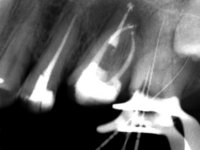

Male patient, 34 years old, non-smoker. Teeth 17 and 16 had extensive restorations with composite resin and placed intra-radicular posts. In the imaging examination, it was found that the endodontic treatment was not technically satisfactory, but had been asymptomatic for several years. The patient was rehabilitated with a 2-element bridge at 17 and 16 and 4 years later an abscess appeared in the apical area of 2.6. It had the 2.8 tooth included with a close relationship with the 2.7 root. During these 4 years there was no positional change of this tooth. After endodontic retreatment of teeth 27 and 26, an abscess appears again in the area of tooth 26, possibly associated with a root fracture. Given the history referred to in relation to tooth 26, it was considered a tooth with indicated extraction.

Teeth 17 and 16 were prepared for the fabrication of a 2-element Zr bridge. The impression was performed with a double mixing technique and a monolithic bridge in Zr was made in the laboratory. 4 years later, an abscess appeared in the apical area of tooth 26. It was decided to remove the bridge, remove the intra-radicular posts and retract the endodontic treatments of teeth 17 and 16. The removal of the bridge was carried out by making two cervical cavities. in the palatal area of the bridge and with a microluxator, disinsertion movements were performed. The intra-radicular posts were removed using fine drills and an ultrasound tip. The bridge was provisionally cemented and the patient was referred to a fellow endodontist for endodontic retreatment. After the retreatment, the intraradicular posts were placed again and the bridge was definitively cemented. One year later, a new abscess appears, possibly related to a root fracture. The bridge was sectioned between tooth 27 and 26 and tooth 26 was extracted and the crown of 27 was provisionally cemented. 3 months later, teeth 27 and 25 were prepared and a temporary bridge was made in dual polymerization resin. Then, an impression was made using the double mixing technique and a 3-element bridge in Zr was made in the laboratory. It was permanently cemented in the mouth with resin-reinforced glass ionomer cement.